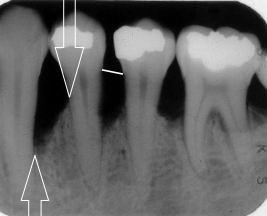

vertical bone loss

seen on radiographs as a non parallel line of bone loss

bone loss with furcation involvment

first sign of vertical bone loss

PDL space widens towards the crest

vertical bone loss M/D of #2